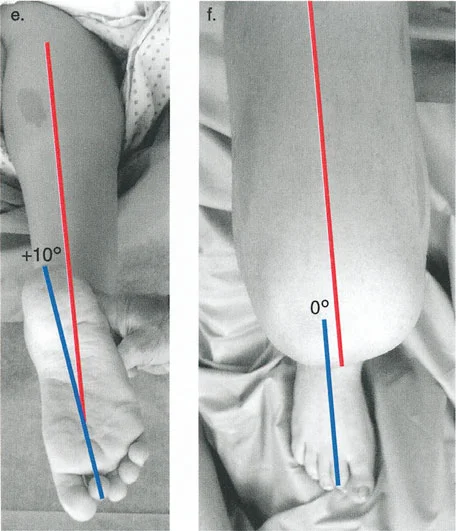

- فحص الدوران المحوري للأطراف (على سبيل المثال، محور الفخذ-القدم لدوران الساق).

- التصوير المقطعي المحوسب (CT Scan): يُعد حاسمًا لتقييم التشوهات الدورانية (الالتواء) التي لا تظهر بوضوح في الأشعة السينية التقليدية، ولإجراء قياسات ثلاثية الأبعاد دقيقة للعظم.

لتصحيح التشوه، يجب أولاً تعريفه بدقة. يمكن للعظم في الفضاء ثلاثي الأبعاد أن يتشوه بالنسبة لجزئه الطبيعي بست طرق مميزة، تُعرف باسم درجات الحرية الست. تُصنف هذه الدرجات إلى إزاحات ودورانات على طول المحاور التشريحية الثلاثة (التاجي، السهمي، والمحوري).

- الدوران المحوري (الالتواء):

- الدوران الداخلي (Internal torsion): التواء حول المحور الميكانيكي نحو الداخل.

- الدوران الخارجي (External torsion): التواء حول المحور الميكانيكي نحو الخارج.